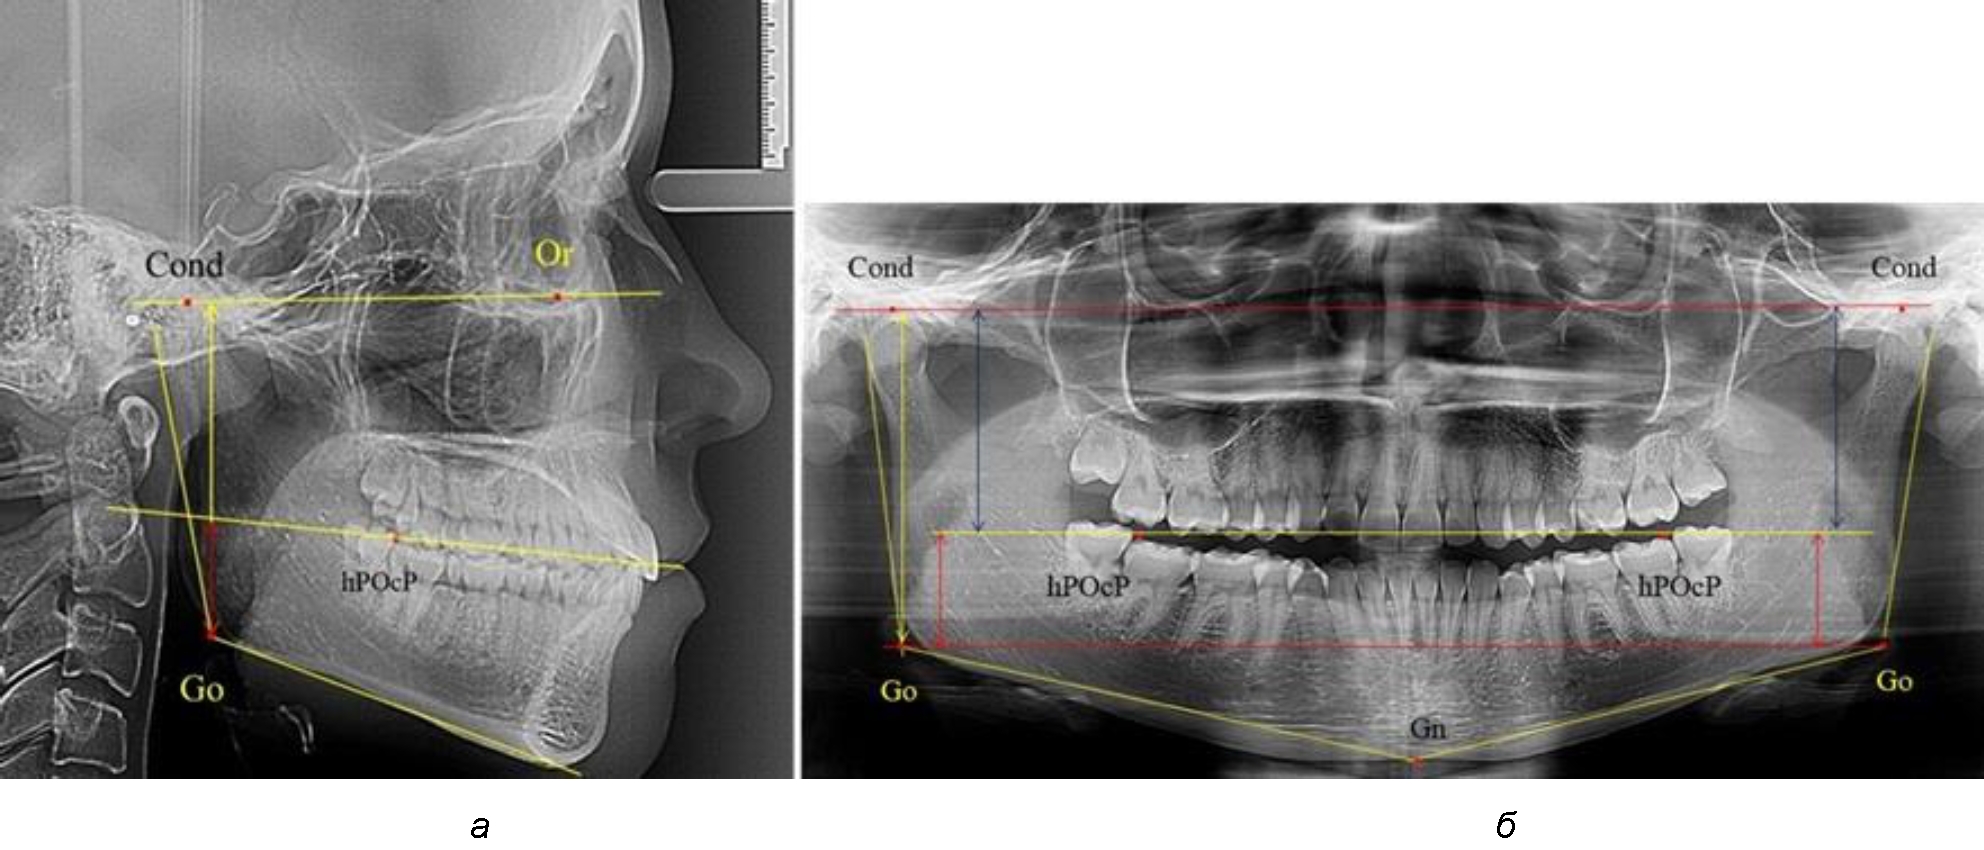

Рис. 1. Метод измерения высоты ветви нижней челюсти на телерентгенограмме (а) и ортопантомограмме (б)

На боковых телерентгенограммах определяли положение верхней точки суставной головки Cond. Касательные линии к ветви и телу нижней челюсти пересекались в точке, которую в клинической практике обозначают как точка угла нижней челюсти или точка гонион Go. Точкой hPOcP обозначали дистальный бугорок нижнего второго моляра вблизи окклюзионного контура коронки, через нее от межрезцовой точки проводили окклюзионную линию, ее продолжали до задней части ветви челюсти. Высоту ветви измеряли как расстояние от угла нижней челюсти до вершины суставной головки Go-Cond. Общую высоту ветви условно делили на 2 части, ее границей служила окклюзионная линия. Верхнюю часть обозначали как окклюзионно-суставная, а нижнюю – как окклюзионно-гониональная.

На ортопантомограмме использовали аналогичные суставные точки Cond на каждой стороне, их соединяли между собой суставной линией Cond-Cond.

Касательная к ветви нижней челюсти соединяла выступающие точку. При построении касательной к телу челюсти проводили в обе стороны линии от точки Gn, расположенной в нижней центральной части подбородочного симфиза, до выступающей нижней точки угла челюсти. Касательные линии при пересечении определяли конструктивную точку гонион Go. Соединение гониональных точек определяло положение гониональной линии Go-Go. При соединении окклюзионных точек hPOcP получали окклюзионную горизонталь (рис. 1). Измеряли расстояние между горизонталями в области ветвей нижней челюсти. Статистический анализ проводили в программе Microsoft Excel. Составляли вариационные ряды с последующим расчетом среднего значения, стандартного отклонения и ошибки среднего ±m. Также оценивали максимальные и минимальные значения величин. Определи относительные величины соотношения верхней и нижней частей ветви нижней челюсти.